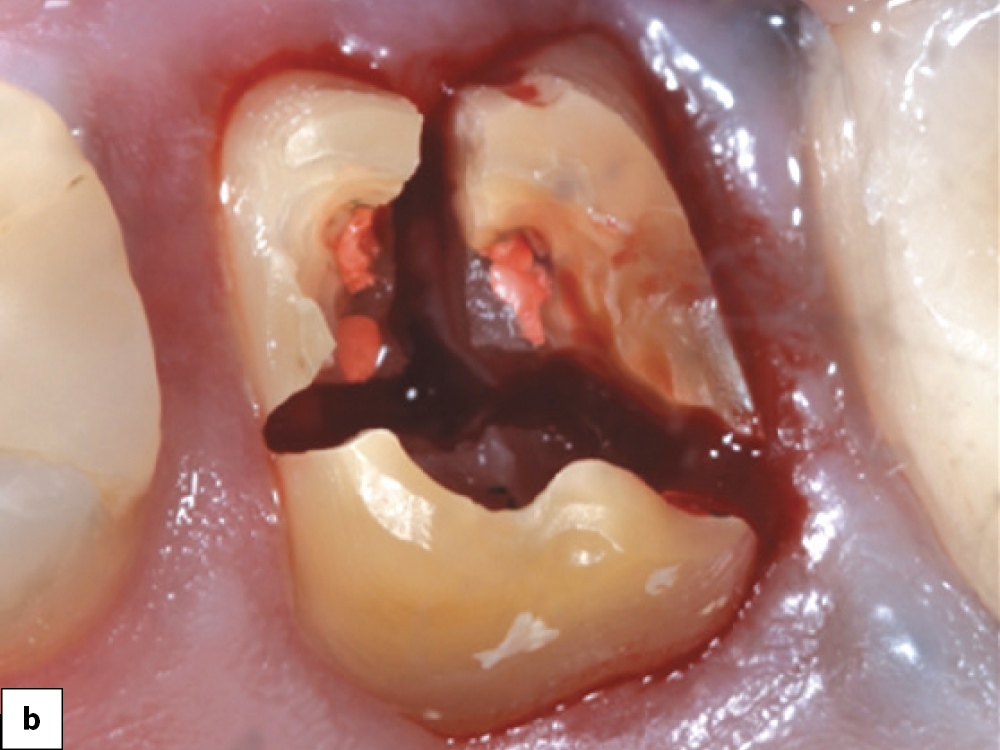

Bony Defect Evaluation A

Bony Defect Evaluation B

Bony Defect Evaluation C

Bony defect evaluation: (a) Flap reflection allows the clinician to visually evaluate the size and location of the fenestration to determine whether the defect will compromise implant positioning or primary stability when immediate implant placement is desired; (b) Examples of a large fenestration (green arrow) and loss of the buccal plate (blue arrow), either of which would contraindicate immediate implant placement due to the inability to obtain primary stability; (c) Additional example of flap reflection to show the fenestration.